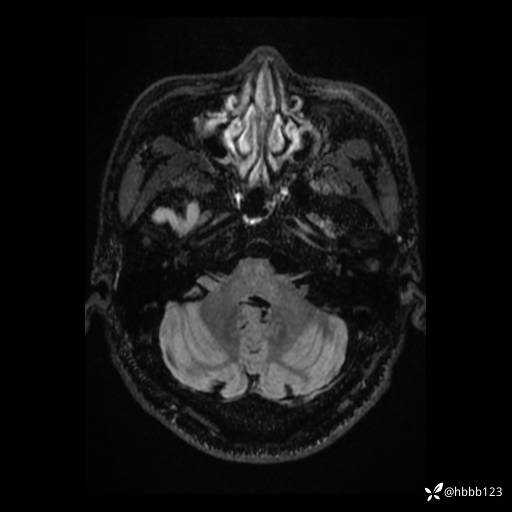

患者男,43岁。

简要病史:癫痫患者复诊,昨日发作5-6次,建议住院进一步治疗。

入院完善脑癫痫组合序列:

T2: